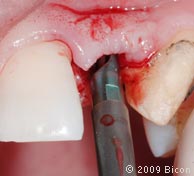

62. Излишки композита с межпроксимального контакта удаляются с помощью полировочной штрипсы с алмазным напылением. Это необходимо для облегчения процесса активации конусного соединения.

63. При помощи полировочной штрипсы с алмазным напылением удаляем излишки композита с межпроксимального контакта, чтобы облегчить активацию конусного соединения.